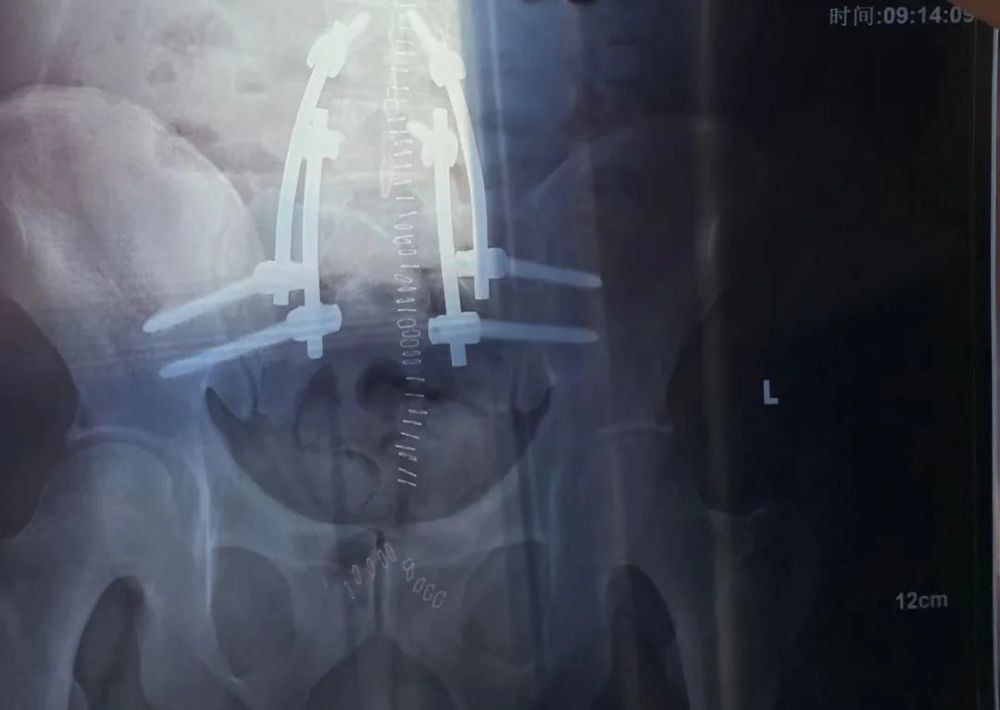

麻醉药的效果还在,我没有感觉到什么痛苦,也没关心过自己到底经历了什么。但是查房的时候,医生一下子掀开了被子,我才看到自己身上插着三根管子,两根引流管、一根尿管。800毫升,不是啤酒,是我一晚上引流出来的盆腔血水。我多么希望自己可以一跃而起,顺手拔了管子,然后从手上伸出钛合金的爪子,从此哥们就是金刚狼本狼了。

然而事实上,我坐不起来也拆不了管子,我和金刚狼唯一的共同点是我身体里也有一堆钛合金支架,但它们可千万别从我身体里伸出来。

我的钛合金支架丨作者供图